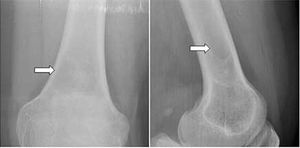

Case History: 58-year-old male with intermittent mild pain in left knee. No previous remarkable trauma; no correlation between pain and physical activity.